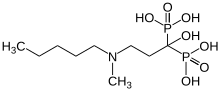

Bisphosphonates

Les bisphosphonates sont – avec les anticorps anti-RANKL (Denosumab) – les seuls médicaments destinés tout particulièrement au traitement des métastases osseuses. Jusqu'à présent ils étaient considérés comme le nec plus ultra[138]. Mais leur utilisation est purement palliative et pas curative[5],[48],[63].

Les bisphosphonates ont été développés initialement pour le traitement de l'ostéoporose. Ils stabilisent les os fragiles en se liant particulièrement fort avec le tissu osseux. Ceci rend plus difficile la dégradation du tissu osseux par les ostéoclastes. Les bisphosphonates sont en général bien supportés et peuvent être administrés en même temps qu'une hormonothérapie ou une chimiothérapie. Les bisphosphonates modernes, comme l'acide zolédronique sont efficaces rapidement et pour longtemps. L'acide zolédronique est appliqué par perfusion. Il existe des bisphosphonates disponibles pour la voie orale, comme l'acide clodronique ou l'acide ibandronique. On peut commodément les prendre sous forme de comprimés par voie orale, ils sont très bien supportés par les reins et bien adaptés à une thérapie au long cours[6]. Ils ne diffèrent que marginalement en efficacité des divers autres bisphosphonates[139]. Les bisphosphonates réduisent en outre les douleurs osseuses provoquées par les métastases[140],[141].

L'nécrose osseuse associée au bisphosphonate dans la région du maxillaire sont un effet secondaire des bisphosphonates décrit depuis 2003[142]. Cette modification osseuse est caractérisée par une ostéonécrose secondaire à une oblitération vasculaire, limitée aux maxillaires[143].

Une discussion fait encore l'objet de controverse : savoir si l’administration de bisphosphonates avant la survenue de métastases osseuses peut avoir une action préventive, voire anti-tumorale[144],[145]. Les études effectuées jusqu’à présent ne donne pas de vision uniforme[6]. In vitro, l'acide zolédronique a la propriété de réprimer les métastases osseuses, de diminuer la prolifération cellulaire et de remonter le taux d'apoptoses[146].